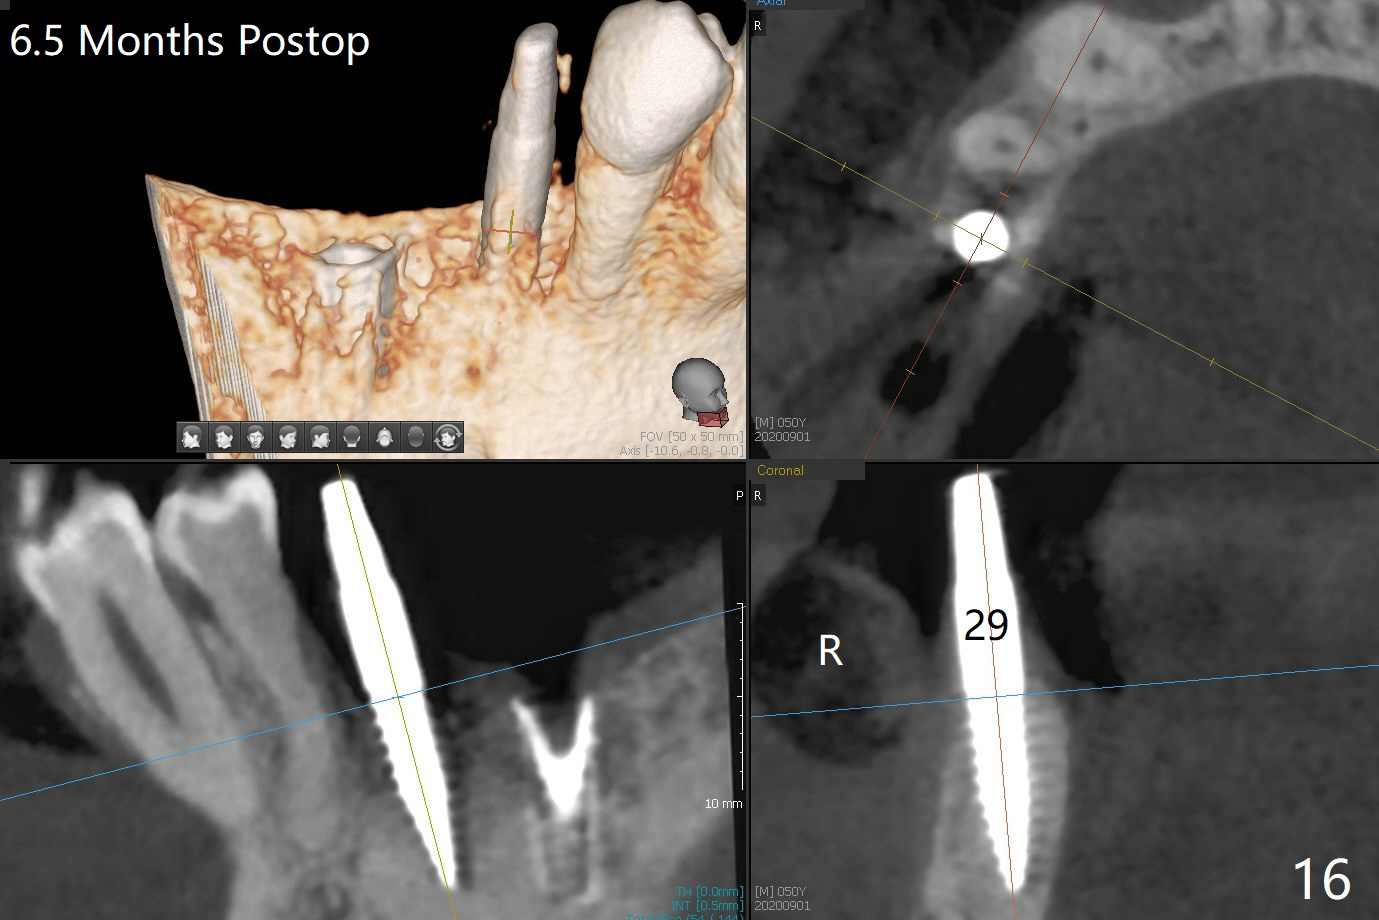

The implant at #30 was also buccally placed (Fig.6,7) and should be corrected in the same manner (Fig.7 green). Due to the bone being harder in the molar region, a smaller and shorter implant (4x11 mm vs. 5x13 mm) shifts slightly buccally while being placed (Fig.8,9). Since primary stability is lower (<20 Ncm vs. 35 Ncm associated with the implant #29), an abutment is not placed, which may be favorable to healing, but it is difficult to achieve primary closure. After bone graft (Fig.9 *) and 2 layers of PRF, Cytoplast is placed. Cytoplast appears to be exposed buccally (Fig.10 <) and occlusally (Fig.11 ^) asymptomatic 9 days postop. Exposure of Cytoplast is more distinct without sign of infection 15 days postop (Fig.12). The patient returns with chief complaint of "foul smell" 7 weeks postop (coronavirus lockdown). Although the Cytoplast exposes more (Fig.13 (* exposed; @ unexposed)), the underlying gingiva remains healthy (Fig.14). While the bone height decreases at #29, the bone density at #30 increases 4.5 months postop (Fig.15). The gingiva heals. The implant at #30 is uncovered 6 months postop. The lingual plate has to be removed for the uncover, while the coronal end of the buccal one is missing. No bone graft is added. When the 4.5x4 mm healing abutment is removed 6.5 months postop, the buccal plate looks concave at #30 (Fig.16' *). The buccal plate looks thin at #29 with a cotton roll placed buccally (Fig.16 R). The lingual plate at #29 is coronal to the buccal one (Fig.17). The buccal gingiva at #29 is quite long (Fig.18). The coronal buccal plate appears to be missing (Fig.19 >), which will be watched. A 4.5x7.5(4) mm cemented abutment is torqued (Fig.20).